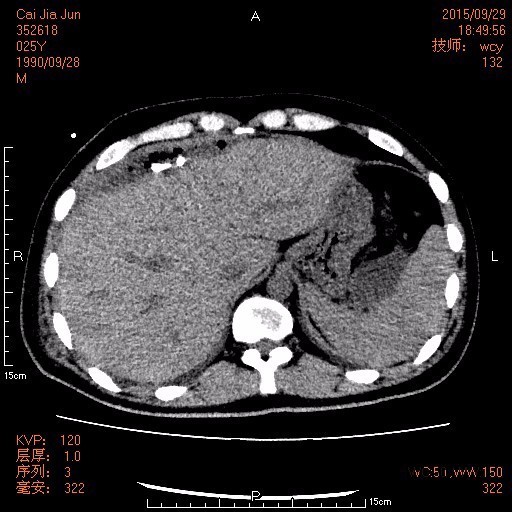

查体: 腹部平软,右下腹及右上腹可见两条引流管,引流出棕色臭味脓液,右下腹有压痛、反跳痛,余腹无压痛及反跳痛。 辅查: 1.腹部CT:1.原阑尾炎穿孔并周围及腹盆腔多发包裹性脓肿形成治疗后复查,现累及范围如上述,与前对比盆腹腔多发脓肿明显吸收变小。 2.腹膜炎;腹腔少量积液,与前对比减少。 3.双侧胸腔积液,与前对比减少;双肺下叶节段性肺不张,较前复张。 4.肝多发小囊肿。 2.胸片:1.右侧胸腔中量积液,左侧胸腔少量积液。 2.双下肺炎症及肺压缩性不张。 3.腹腔引流液培养:大肠埃希菌;屎肠球菌(D群)。

诊断:阑尾穿孔并腹腔脓肿形成。 治疗:伤口换药、抗感染、补白蛋白、控制血糖等处理,复查CT见腹腔包裹性脓肿明显吸收变小,予拔除引流管,无明显发热,予办理出院。